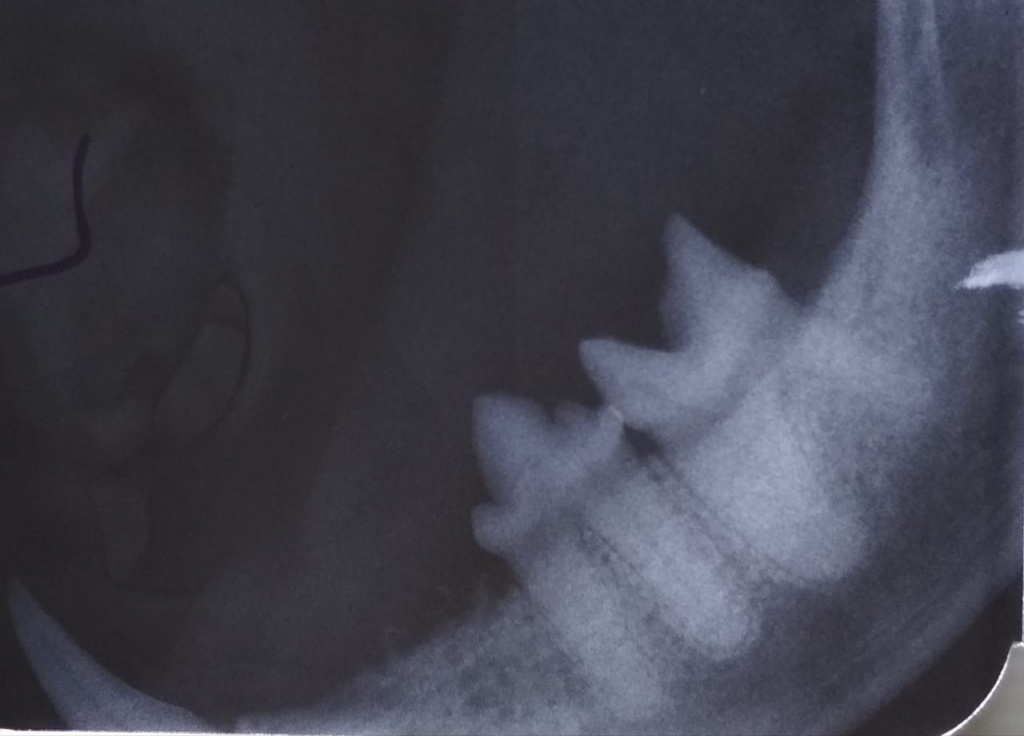

3. Далее выполняется интраоральная рентгенография, необходимая для оценки состояния корней, костных структур, периодонтальной связки и т.д.